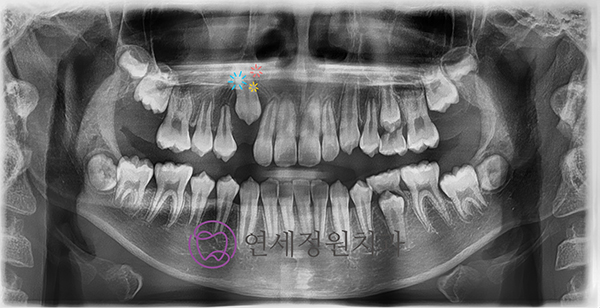

위 환자의 경우 왼쪽 송곳니가 내려올 공간은 부족하고 오른쪽 앞니도 안으로 들어가서 나와 반대로 물리고 있었습니다. 그리고 오른쪽 두번째 작은 어금니 또한 앞뒤 치아에 걸려서 내려오지 못하고 있었습니다. 물론 나중에 성인이 된 이후에 교정을 해도 되겠지만(발치 교정을 해야 할 가능성이 높아지겠죠), 커서 복잡한 치아 교정을 안해도 될 수 있도록 다른 치아들이 맹출하기 전에 미리 공간을 만들어주기로 하였습니다.

치과대학에서 원내생 실습을 하는 동안 가철성 교정장치를 만드는 실습을 하는데, 그 때 점수도 가장 높고 가장 만들기 어려운 장치가 하나 있었는데요... 바로 이런 케이스를 교정해주기 위한 "sagittal appliance" 입니다. 이 장치의 역할은 송곳니가 맹출할 수 있는 공간을 확보하기 위해 앞니는 앞으로 밀어주고, 어금니는 뒤로 밀어주는 장치입니다.

위 환자의 경우 안으로 들어와있는 앞니도 밀어주고 공간이 부족해서 나오지 못하고 있는 작은 어금니 공간도 마련해주기 위해 sagittal appliance에 앞니를 밀어주기 위한 push spring과 작은 어금니 공간을 마련해주기 위한 distal screw도 추가해주었습니다. 이 정도면 10점짜리 최고난이도 장치가 아닐까 싶습니다 ^^;;

Sagittal appliance with distal screw and push spring